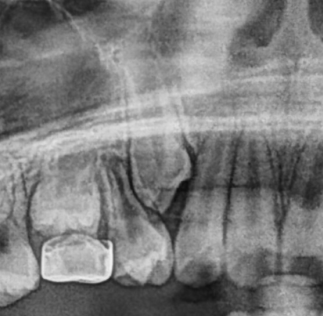

아이 유치가 빠졌는데 송곳니가 한참을 기다려도 나오지 않았어요ㅠㅠ 주변에서는 기다려보라는 말도 있었고, 안되겠다 싶어서 이미인교정치과에 가게 되었어요.

정밀검사해 보니 잇몸 안에 송곳니가 매복돼 있다고 하셨고, 치료비용도 분납할 수 있어서 부담이 없길래 바로 하기로 했었어요. 교정하는 동안 아이도 잘 따라줬고,

혹시 임플란트 해야 할까 봐 정말 많이 걱정했는데,